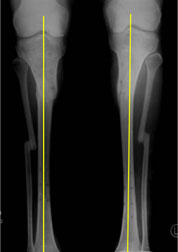

The final x-ray pictures after fixator removal, showing excellent correction and a good bony union. |